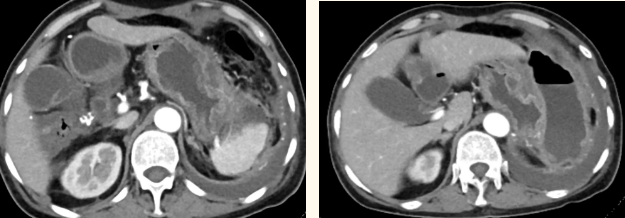

患者李阿姨早在7年前就確診為胃間質(zhì)瘤,并伴有肝臟轉(zhuǎn)移。一直以來,李阿姨都依靠口服藥控制腫瘤。令她意外的是,近2年胃間質(zhì)瘤增大了,最大時(shí)約為17.7 cm?12.2 cm?15.8cm,侵犯脾臟,并出現(xiàn)消化道出血,反酸。李阿姨也吃不下飯,睡不好覺,體重明顯下降。

一籌莫展的她終于在病友的介紹下,來到西安國(guó)際醫(yī)學(xué)中心醫(yī)院找到蔡磊主任。經(jīng)過詢問病史,查體等,蔡磊主任建議口服索坦治療。3個(gè)月后,李阿姨復(fù)查CT提示胃間質(zhì)瘤較前明顯縮小,大小約10.4cm?6cm。但仍存在消化道出血,營(yíng)養(yǎng)狀況差,全身無力,骨髓抑制。蔡磊主任隨即將患者收治入院。